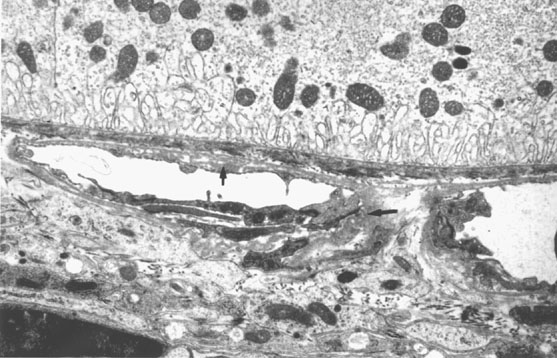

Figure 7. Choriocapillaris in a mouse model of protoporphyria

In the mouse model of protoporphyria with approximately a 10-fold increase in protoporphyrin IX and exposure to blue light (380-430 nm, 14 µW/cm2), a time and light dependent increase in choriocapillary and subretinal pigment epithelial basal laminar-like deposits are demonstrated (see arrows).